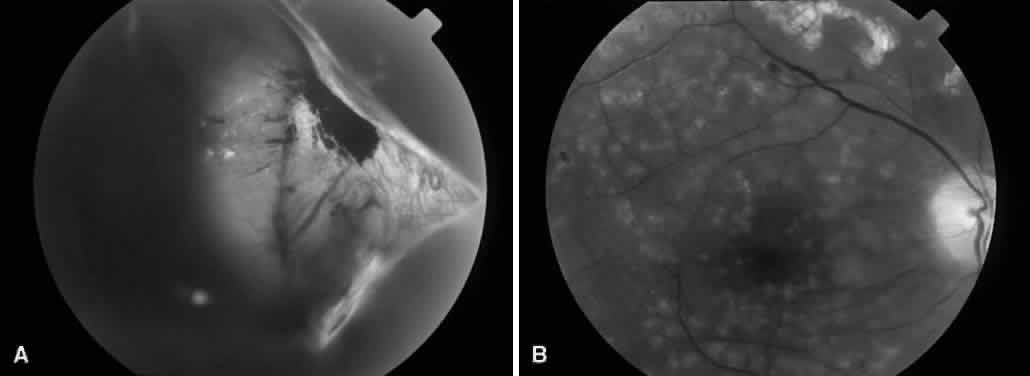

COMBINED TRACTION-RHEGMATOGENOUS RETINAL DETACHMENT

Vitreous traction and contraction of proliferative tissue can produce retinal tears, leading to combined traction-rhegmatogenous detachments. Unlike purely tractional detachments, extramacular rhegmatogenous detachments frequently progress to involve the macula, leading to rapid and severe visual loss. Thus, surgical repair is indicated in combined detachments, whether or not the macula is involved. Often, the retinal breaks are located posterior to the equator, adjacent to areas of fibrovascular proliferation that are under severe vitreoretinal traction. Therefore, this condition is difficult to treat by conventional scleral buckling methods, whereas vitrectomy (with or without scleral buckling) is effective in treating this condition (Fig. 5). Intraocular long-acting gas tamponade is required to treat these detachments. Combined traction-rhegmatogenous detachments have a lower success rate than pure tractional detachments or nonclearing vitreous hemorrhage. In an analysis of 172 eyes that underwent vitrectomy for combined traction-rhegmatogenous diabetic retinal detachment, 48% had an improved visual acuity on final examination.21 A final visual acuity of 20/100 or better was achieved in only 25% of eyes, and a final visual acuity of 5/200 was achieved in 56%. Visual loss progressed to no light perception in 23% (compared with 19% for macular traction detachment and 6% for nonclearing vitreous hemorrhage). Preoperative factors associated with a favorable visual prognosis included visual acuity of 5/200 or better, absence of iris neovascularization, and absence of retinal detachment involving the macula. The only intraoperative factor found to be associated with a favorable visual prognosis was the absence of iatrogenic retinal breaks.

Fig. 5. A. Preoperative fundus photograph of an eye with combined traction-rhegmatogenous retinal detachment from severe proliferative diabetic retinopathy. B. Postoperative fundus photograph of the same eye after vitrectomy, membrane dissection (using delamination technique), and endolaser photocoagulation.